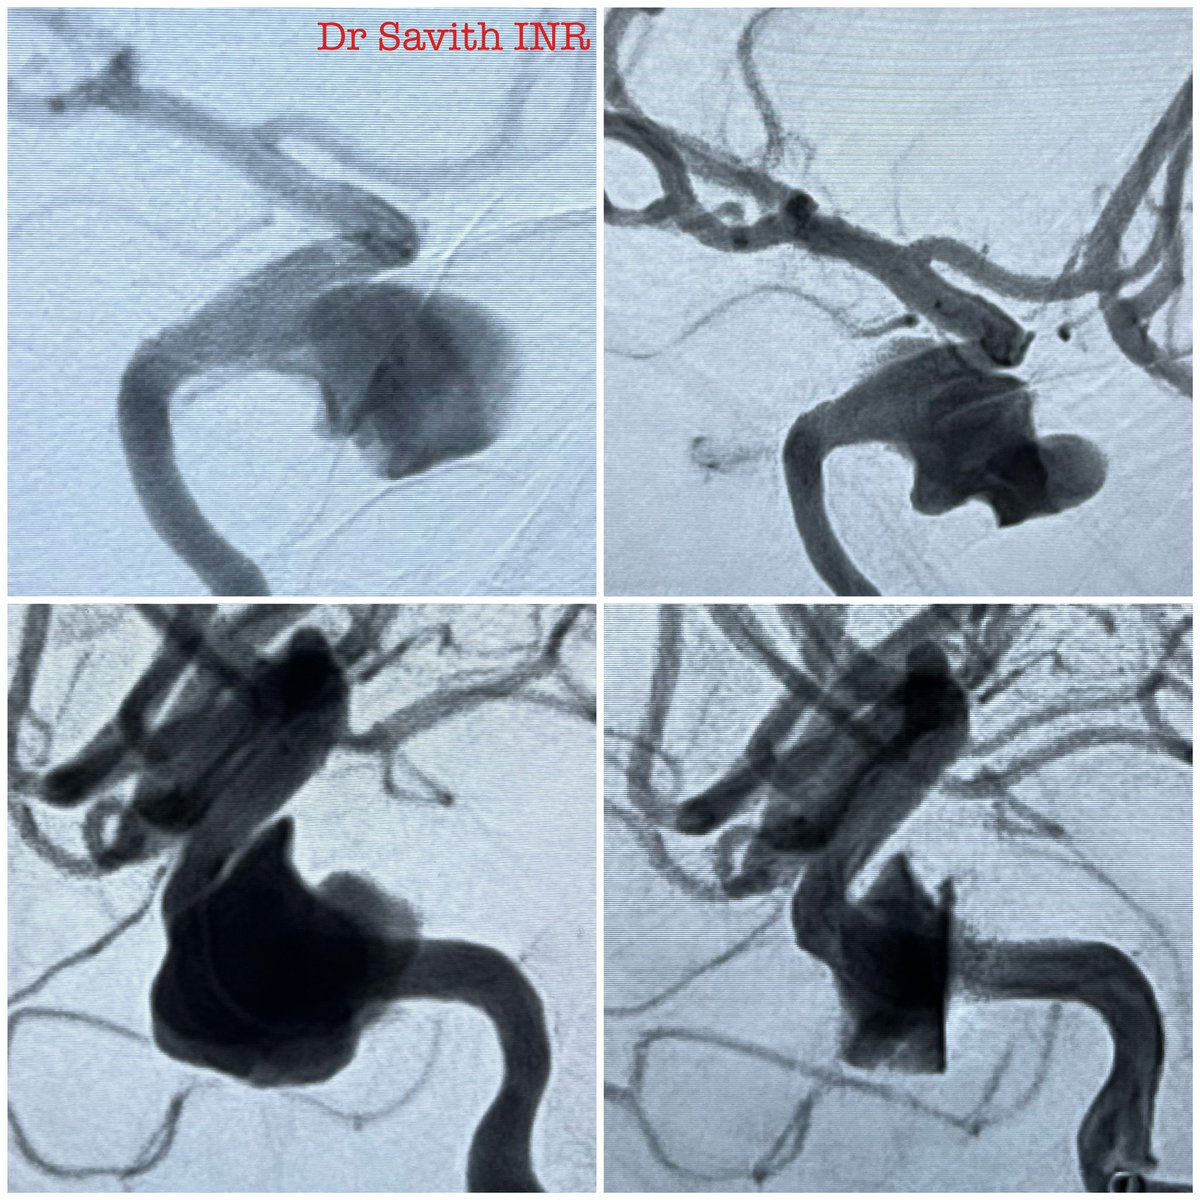

Stent assisted coiling. 71 year old female with wide necked ruptured ACOM aneurysm. Neuroform Atlas with coils. #aneurysm #neurointervention #endovascular #neuroradiology